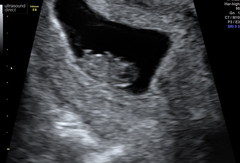

My scan was good too - we saw the heartbeat this morning, measuring exactly what I thought, 7+5. We're now discharged from the EPU, and waiting for the 12-week scan. I cried when we saw it!